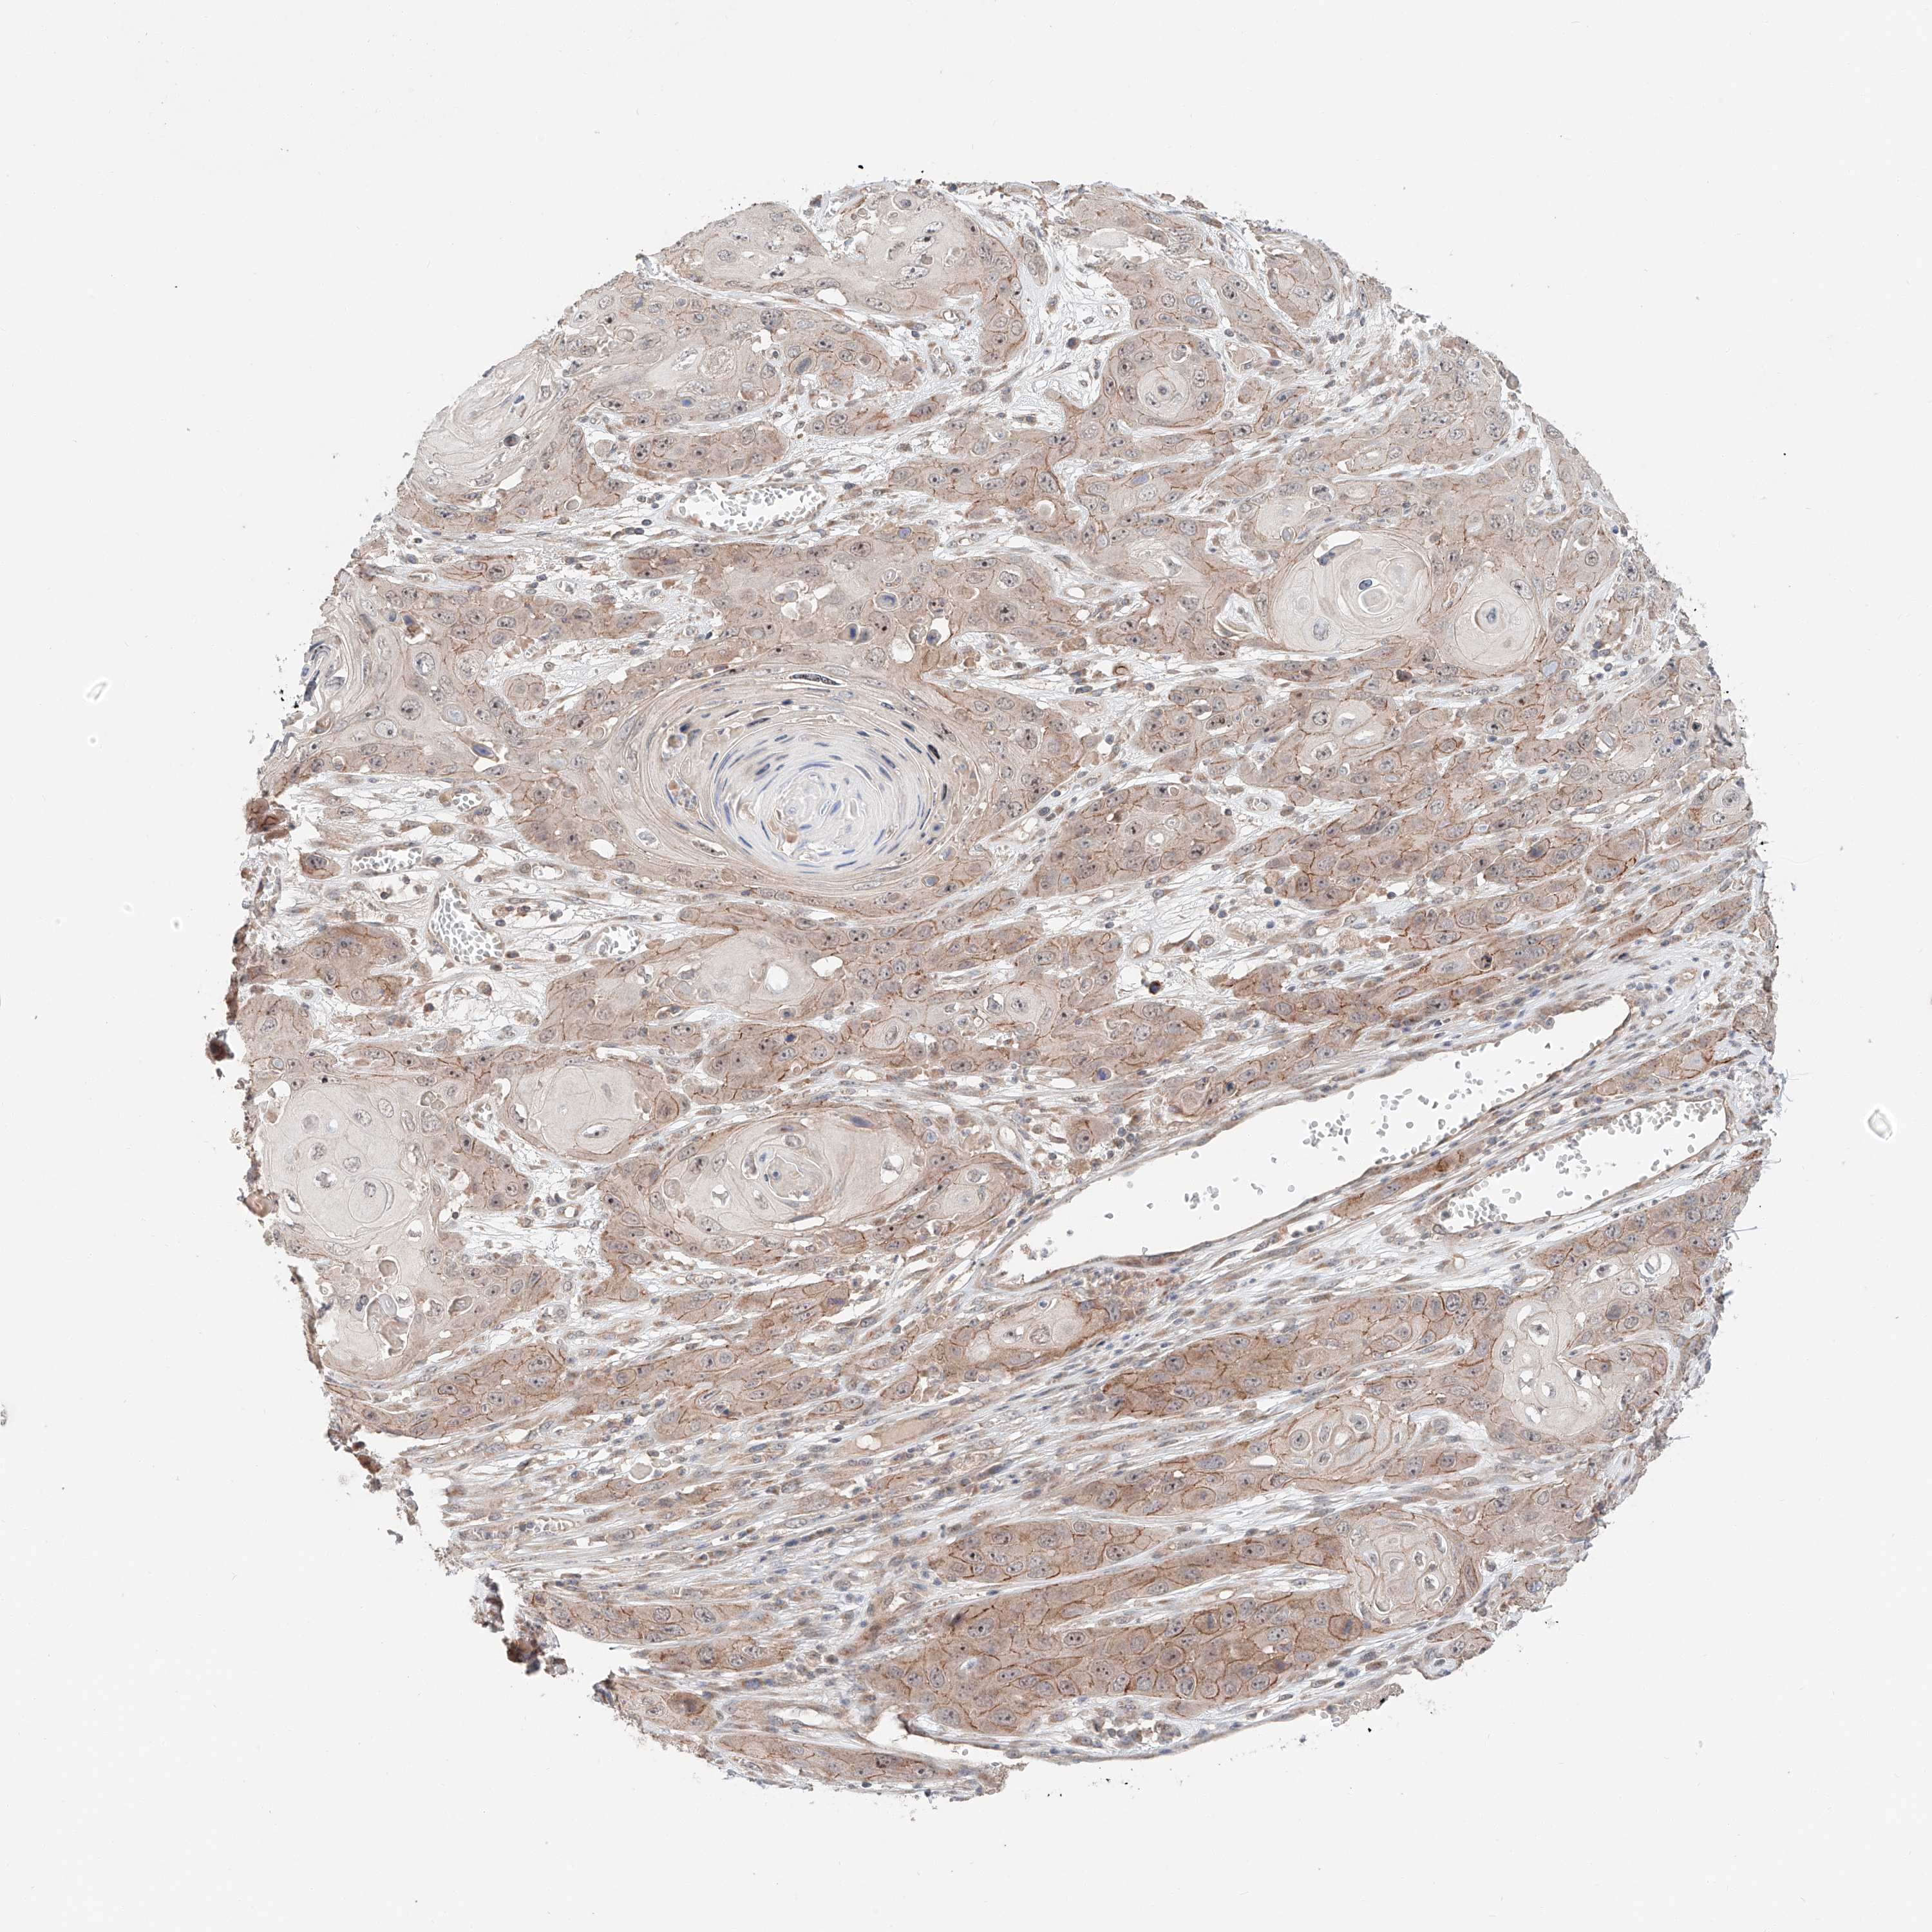

CANCER SKIN CANCER Show tissue menu

Basal cell and squamous cell cancer

SKIN CANCER - Protein expressioni

A mouse-over function shows sample information and annotation data. Click on an image to view it in a full screen mode. Samples can be filtered based on level of antibody staining by selecting one or several of the following categories: high, medium, low and not detected. The assay and annotation is described here.

Antibody stainingi

Antibody staining in the annotated cell types in the current human tissue is reported as not detected, low, medium, or high, based on conventional immunohistochemistry profiling in selected tissues. This score is based on the combination of the staining intensity and fraction of stained cells.

Each image is clickable and will lead to virtual microscopy that enables deeper exploration of all samples and also displays staining intensity scores, fraction scores and subcellular localization as well as patient and tissue information for each sample.

Squamous cell carcinoma, metastatic, NOS